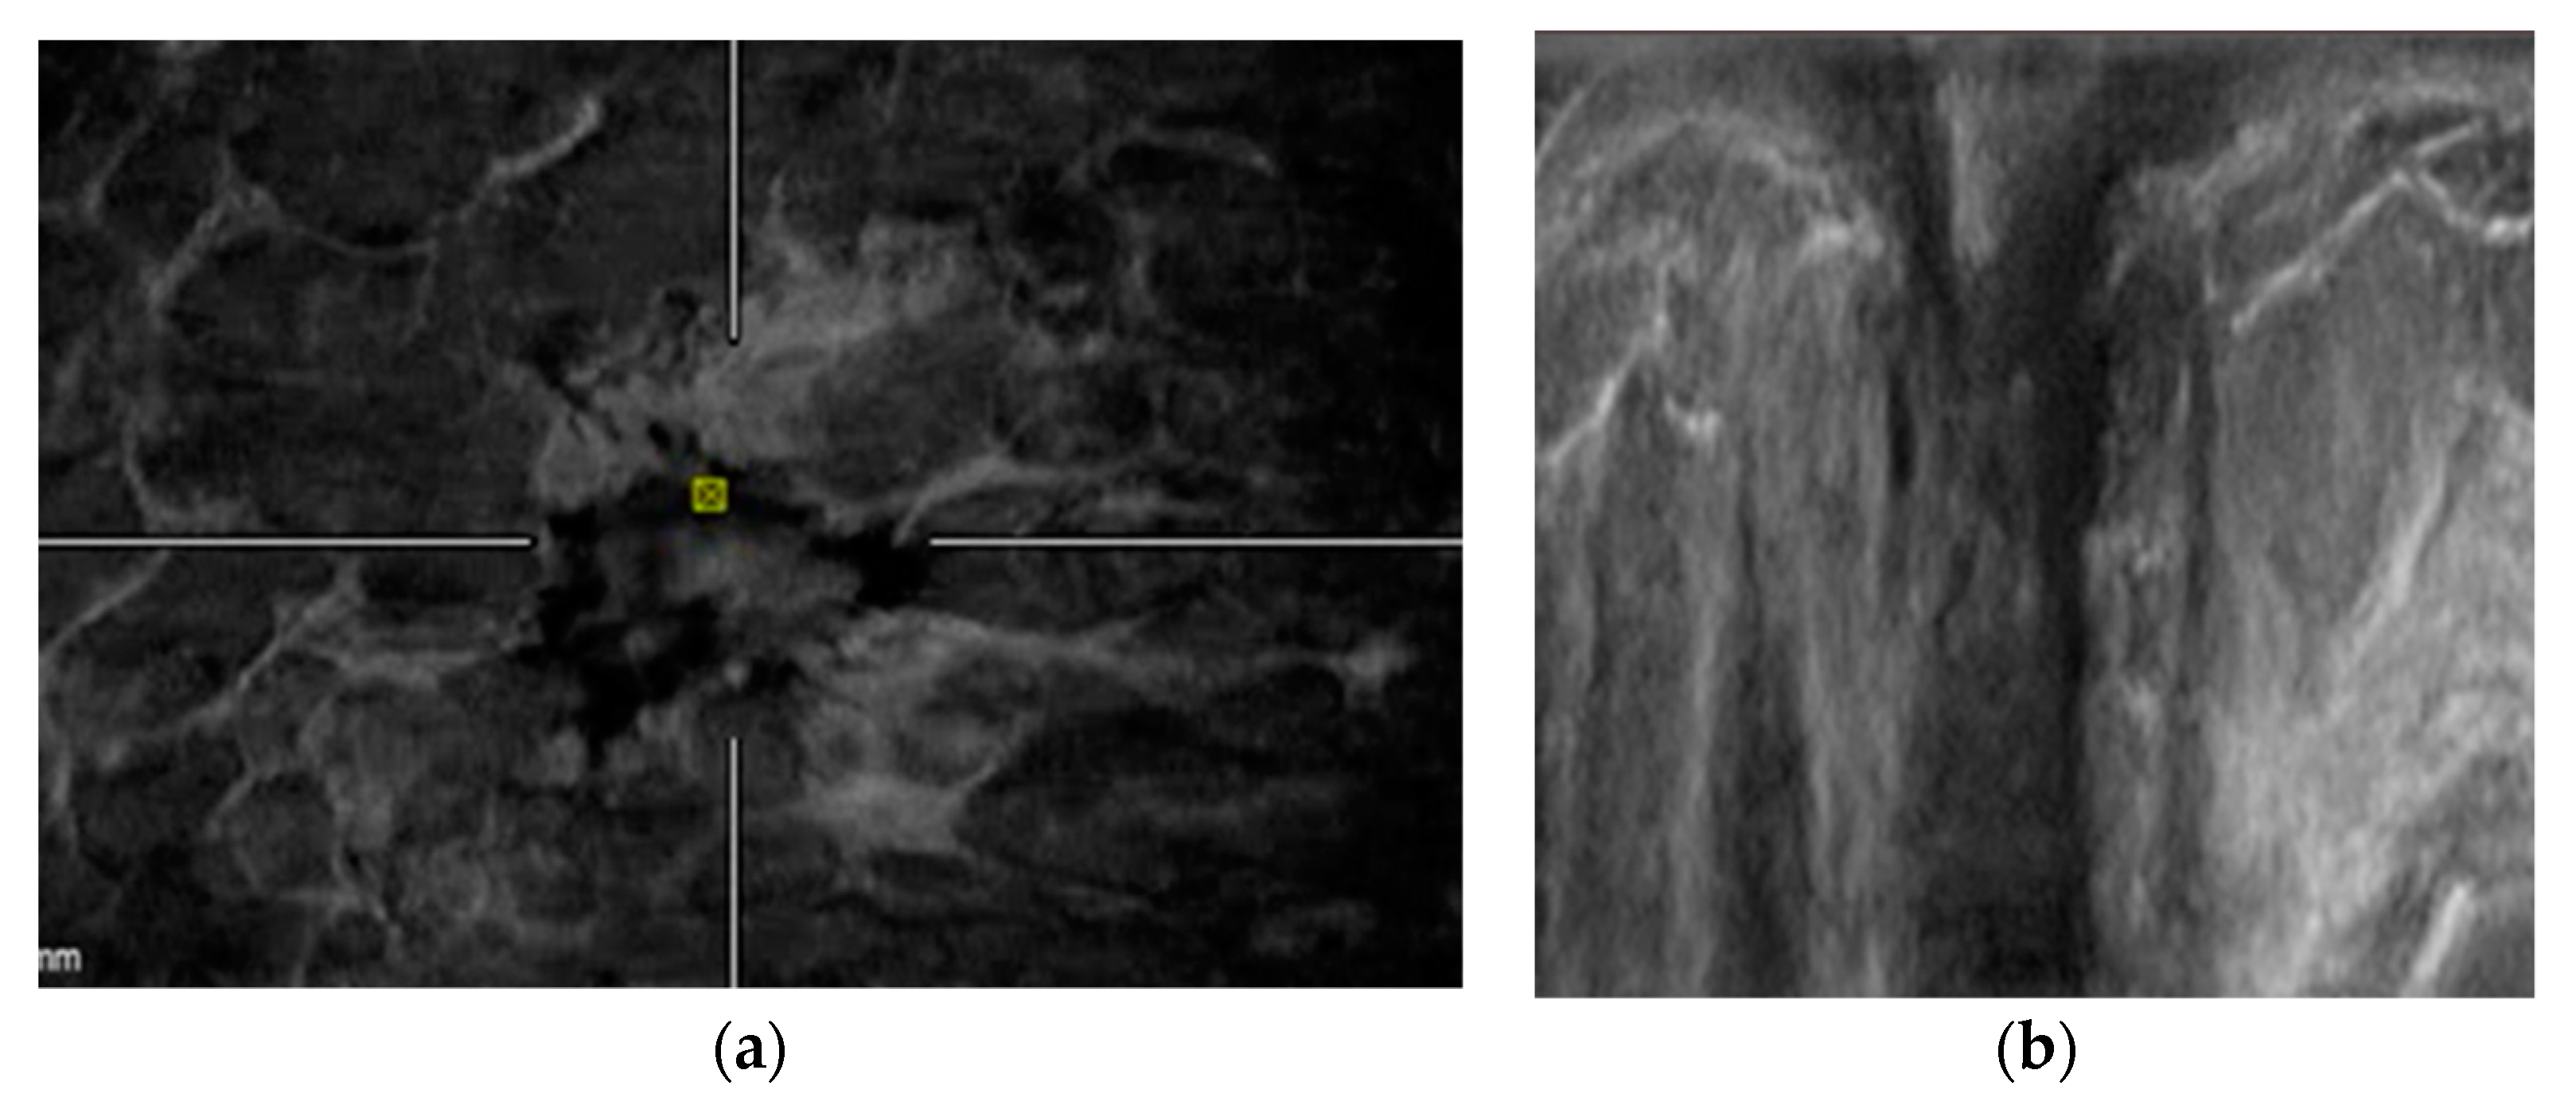

2.4. ABVS Interpretation

- Zheng, F.Y.; Yan, L.X.; Huang, B.J.; Xia, H.-S.; Wang, X.; Lu, Q.; Li, C.-X.; Wang, W.-P. Comparison of retraction phenomenon and BI-RADS-US descriptors in differentiating benign and malignant breast masses using an automated breast volume scanner. Eur. J. Radiol. 2015, 84, 2123–2129. [Google Scholar] [CrossRef] [PubMed]

- Chae, E.Y.; Cha, J.H.; Kim, H.H.; Shin, H.J. Comparison of lesion detection in the transverse and coronal views on automated breast sonography. J. Ultrasound Med. 2015, 34, 125–135. [Google Scholar] [CrossRef]

- Van Zelst, J.C.; Platel, B.; Karssemeijer, N.; Mann, R.M. Multiplanar reconstructions of 3D automated breast ultrasound improve lesion differentiation by radiologists. Acad. Radiol. 2015, 22, 1489–1496. [Google Scholar] [CrossRef]